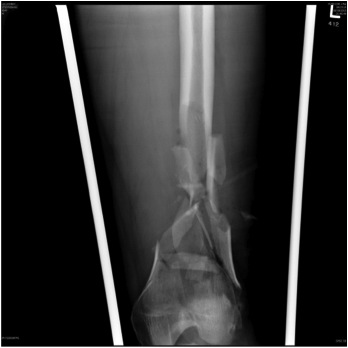

Floating Knee

Ipsilateral femur + tibial fracture

1. Floating Knee

Single incision at knee

- retrograde femoral nail

- tibial IMN if appropriate

High complication rates including non union / malunion, knee stiffness and hetertopic ossification